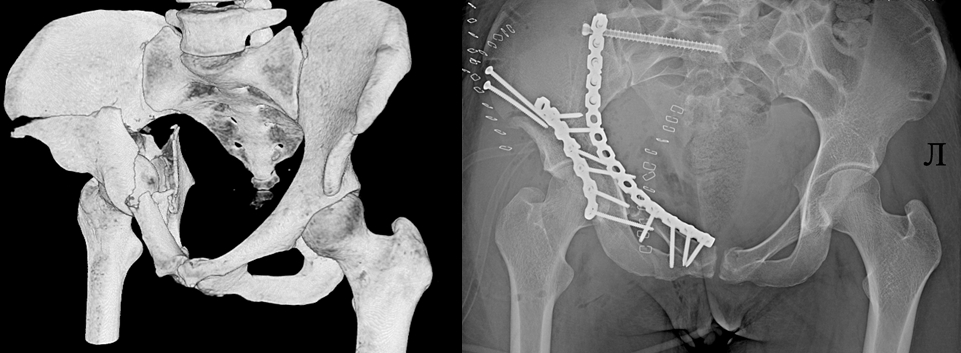

Впрочем, травмы на горках — дело ежегодное и для врачей уже привычное. Тюбинги плохо управляемы, а экстренное торможение почти всегда несёт риск травмы. Последствия таких травм вполне сравнимы с теми, которые пострадавшие получают при столкновении автомобилей на скорости около 60-80 километров в час. Это переломы бёдер, таза, голеней, черепно-мозговые травмы. Причём происшествия случаются не только на «диких» склонах, но и в официальных спортивных парках. А лечение таких повреждений сложное и длительное.

В новогодние каникулы в «соловьёвку» привезли пятерых пострадавших на горках. Наиболее тяжёлые травмы получила 25-летняя девушка. Она, спускаясь с горки на «ватрушке», на скорости врезалась в бетонный блок. Пострадавшую экстренно доставили в больницу, где врачи диагностировали множественные переломы костей таза. Пациентку даже пришлось направить в реанимацию, а после стабилизации состояния — на пятичасовую операцию. Врачи установили сломанные кости в правильном положении и зафиксировали металлоконструкциями. Теперь пациентку ждёт длительная реабилитация.

Фото: ГАУЗ ЯО «Клиническая больница им. Н. В. Соловьёва»